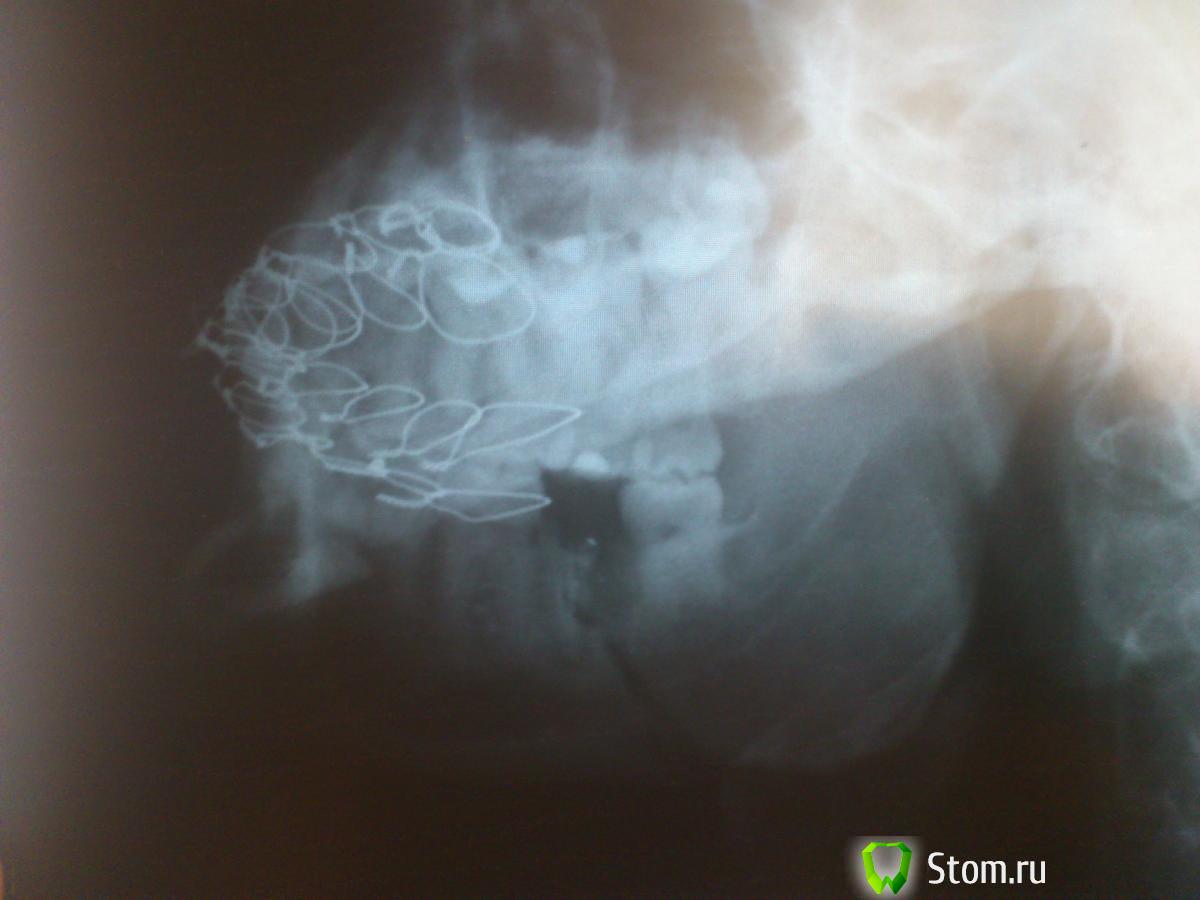

физрук Опубликовано 3 марта, 2012 Поделиться Опубликовано 3 марта, 2012 (изменено) Я сделал снимки через две недели после снятия шин!!Что можете сказать по ним??был перелом в углу нижней челюсти и в области подбородка!! Изменено 3 марта, 2012 пользователем физрук Ссылка на комментарий

ПалСаныч!!! Опубликовано 3 мая, 2012 Поделиться Опубликовано 3 мая, 2012 Эй, чувак, это мой ник!!! Меняй или мне самому придеться подпилить тебе зубы)))Шутка конечно)))Если по делу, то мне кажется рановато снимать шины через 18 дней. Так что все вопросы лучше задай хирургу, что шинировал. Он и снимки видел, и локализацию перелома знает.оооо Извиняюсь, честно, не видел))) ну ничего, я тут почитаю да уйду, надеюсь навсегда))) вот прошла почти неделя как мне сняли шины, эмали НУЛЬ, зубы болят, прикуса нет но уже привык почти. жую еду кое как))) в месте перелома побаливает после того как пожую, думаете пройдет? ну а главный вопрос у меня следующий, на снимке видно что перелом идет от корня зуба мудрости (там даже две трещины, но на снимке плохо видно), что думаете удалять зуб мудрости надо или нет??? а то начитался тут всякого...))) http://s019.radikal.ru/i644/1205/45/6f18b394efcf.jpgссылка на снимок Ссылка на комментарий

kriokov Опубликовано 3 мая, 2012 Поделиться Опубликовано 3 мая, 2012 1. эмаль зубов на месте, ее шинами трудно угробить, после шин бывает повышенная чувствительность зубов, это пройдет. Пасту зубную купите для зубов с повышенной чувствительностью, и к стоматологу терапевту, он проф гигиену проведет2. смещения нет, по этому снимку, прикус скорее всего нормализуется3. Зуб из линии перелома НАДО УДАЛИТЬ, по срокам со стоматологом хирургом определяйтесь.4. болевые ощущения в линии перелома после жевания в течении месяца двух бывают, это нормально, 5. линия перелома у Вас одна, а не две, не переживайте ,просто часто обычный перелом выглядет на снимке в виде двух линий. 1 Ссылка на комментарий